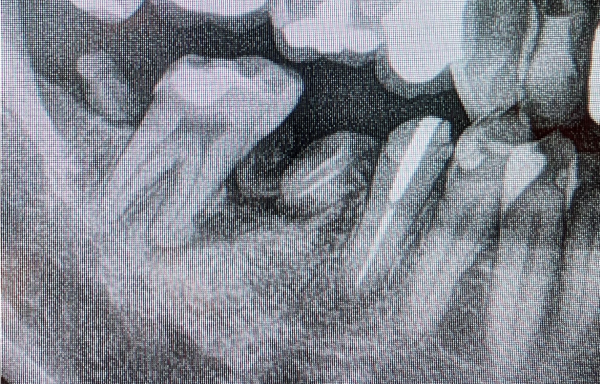

口腔内を確認すると、右下の第一大臼歯(手前側の奥歯)が完全に崩れてしまっていて、さらにはその手前の2本の小臼歯が舌側に倒れ込んでしまっており、歯の側面でギリギリ咬合している状態でした。

しっかり噛めそうなのは第二大臼歯ですが、そちらも虫歯になって半分欠けてしまっている状態でした。その後ろの親知らずは虫歯でほぼ歯がなくなり、かけらになっている状態がレントゲン画像で確認できました。

1枚目の写真は抜歯後3〜4ヶ月後の骨の状態です。斜めに骨が無くなっているのがわかります。